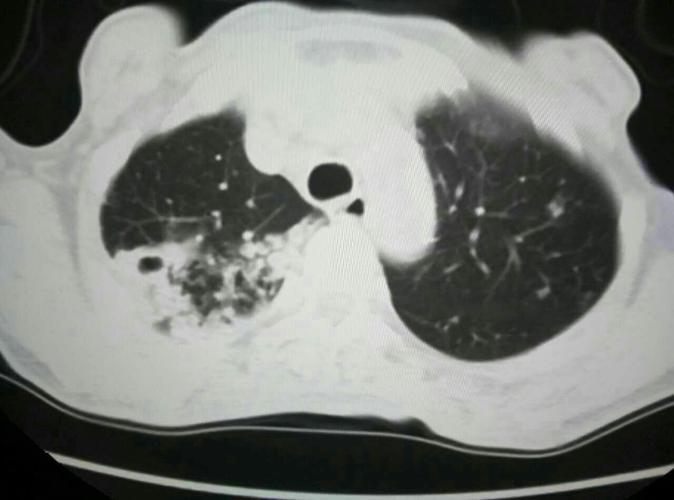

肺结核咳痰带血丝图片,肺结核初期痰的图片

空洞型肺结核